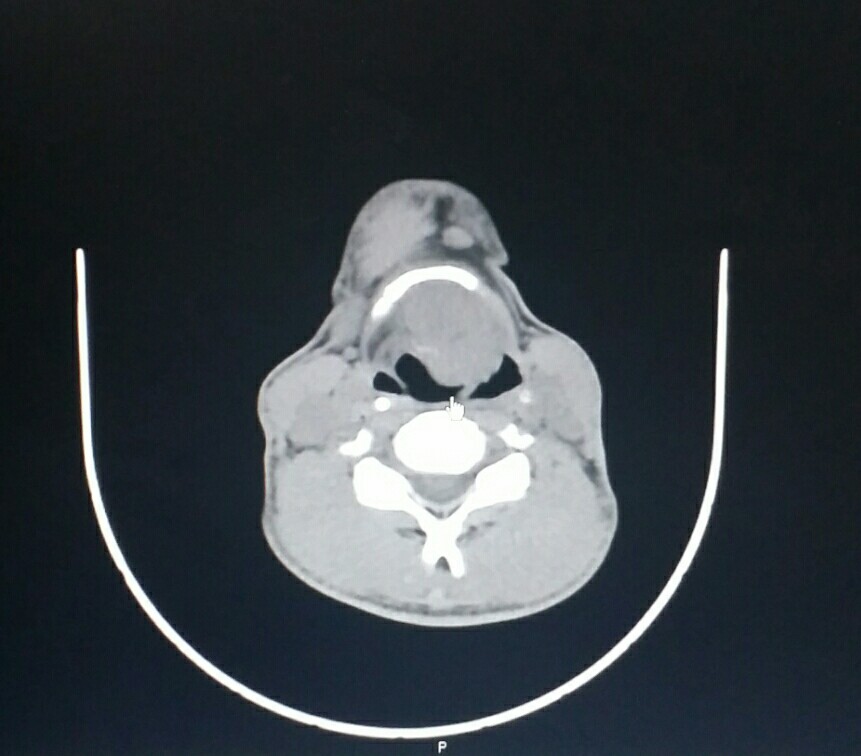

中年男性,颈部不适2月,声音嘶哑半月。自述吞咽是哽噎感。行颈部CT如图,可见喉部肿物,考虑喉癌,必要时增强或者建议喉镜检查,钳取活检。